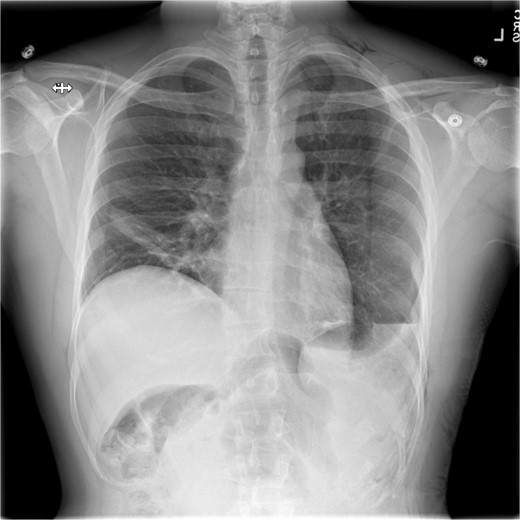

This is a case of a 26-year-old male patient who presented with symptoms of dyspnea on exertion, left chest pressure, and constipation for 7 years. He was a never smoker with no history of trauma, nor prior neck and chest surgeries. Baseline pulmonary functions tests revealed FEV1 of 71% predicted and DLCO of 77% predicted. Work-up included a computed tomography (CT) of the chest which revealed marked left hemidiaphragm elevation with compression atelectasis of the left lower lobe (Fig. 1). A fluoroscopic sniff test showed paradoxical movement of the left hemidiaphragm consistent with diaphragmatic paralysis. Interestingly, abdominal imaging obtained 14 months before surgery showed a displaced stomach but without volvulus (Fig. 2). Due to the impact on the patient’s quality of life, he was offered surgical treatment with a robotic-assisted left thoracoscopic plication of the diaphragm. This was done using a three-arm technique using the Da Vinci Xi surgical system (Intuitive Surgical, Sunnyvale, CA) with an additional assistant port. Plication was performed by placing multiple horizontal mattresses sutures reinforced with pledgets in an anterior–posterior orientation, and systematically working medial to lateral. A postoperative chest X-ray showed a satisfactory result (Fig. 3).

CT from 14-months pre-operation, demonstrating a full, but non-volvulized stomach.